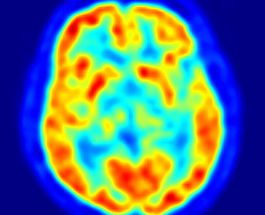

Cercetătorii au descoperit un mijloc eficace de a creşte capacităţile mentale ale oricărui individ injectându-i un curent slab electric pe…